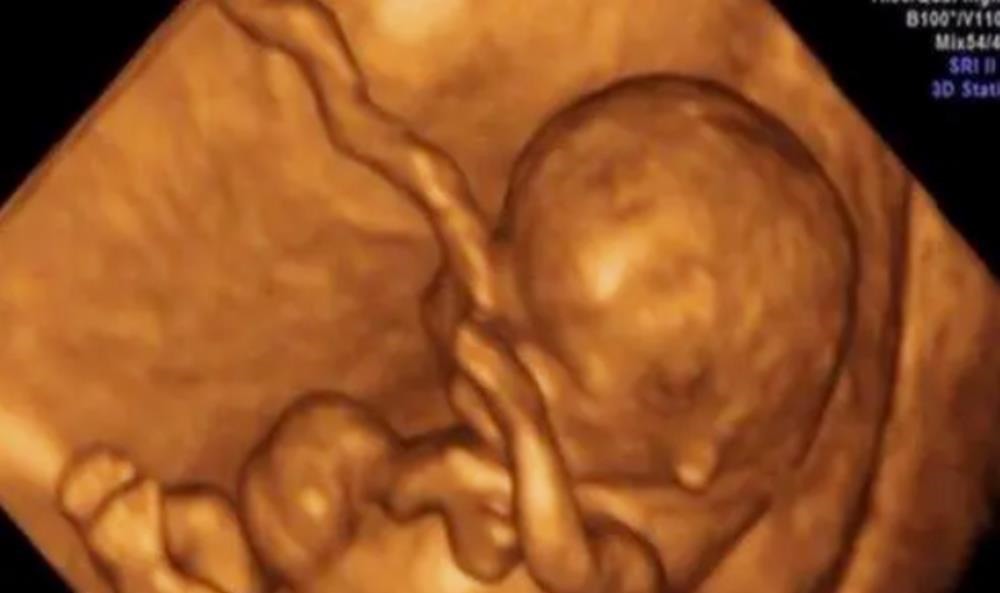

本文由护芽妈妈原创,欢迎个人转发和分享说到孕期检查,就不得不说做“大排畸”时做的四维彩超。随着医学技术的发展,彩超检查也有了显著的提高,如今的四维彩超,不再是仅仅能感觉到宝宝的呼吸和运动,而是能亲眼目睹他们的一举一动和乖巧的笑容。

更重要的是,四维彩超可以多方位、多角度地观察肚子里宝宝的生长发育情况,能更好诊断出胎儿先天发育出现的畸形,所以说,在孕期每个妈妈都需要按照孕检项目做四维彩超。案例玲珑到了要做大排畸的日子,现在大部分孕妈都会选择做四维彩超,即使在费用上会贵上一些,但很多妈妈都觉得无所谓,玲珑也不例外。检查时,医生指着屏幕上那一团模模糊糊的地方,告诉玲珑这个是宝宝的胳膊,这个是宝宝的屁股。其实,玲珑看着屏幕心里满是崩溃,这都是啥啊,土黄的一片,只有彩色的数据来标注血流和心脏,着实是看不懂啊~

三维彩超和四维彩超都是在同一个机器上完成,图像的分辨率和清晰度也都是一样的,唯一的区别就是前者是静态的,后者是动态的。所以说,在做检查的时候,可以先问问医生,有没有给视频这项服务,然后再做选择也不迟。四维彩超后的视频有哪些意义?四维彩超如果能成像,孕妈还是要记得以视频的形式保留一份,因为这份图像可以说是宝宝第一张照片的留念。另外,通过视频来看宝宝状态、轮廓、表情、动作等,会让父母真正看到了一个生命的表现和存在,而不是单纯地存在于妈妈的肚子里。